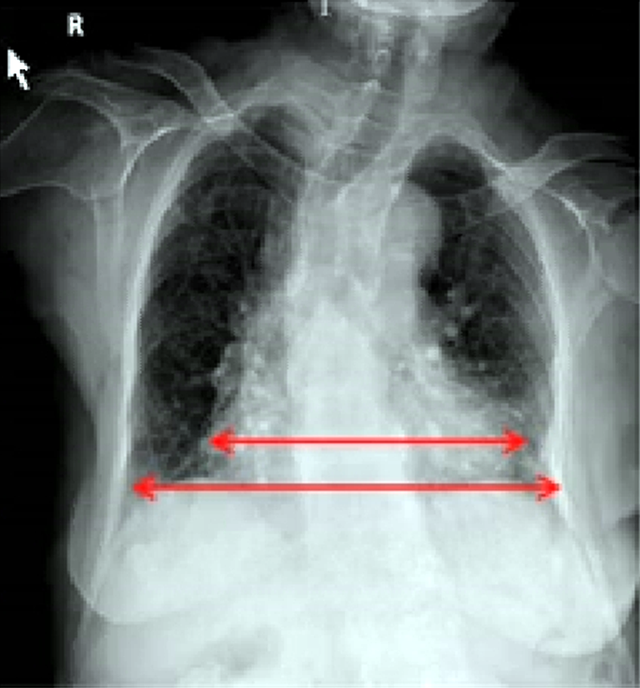

放射科数字dr胶片胸片正位异常片

门诊胸片如下图所示:患儿,男,1 岁 2 月,因「咳嗽 4 天发热 2 天」